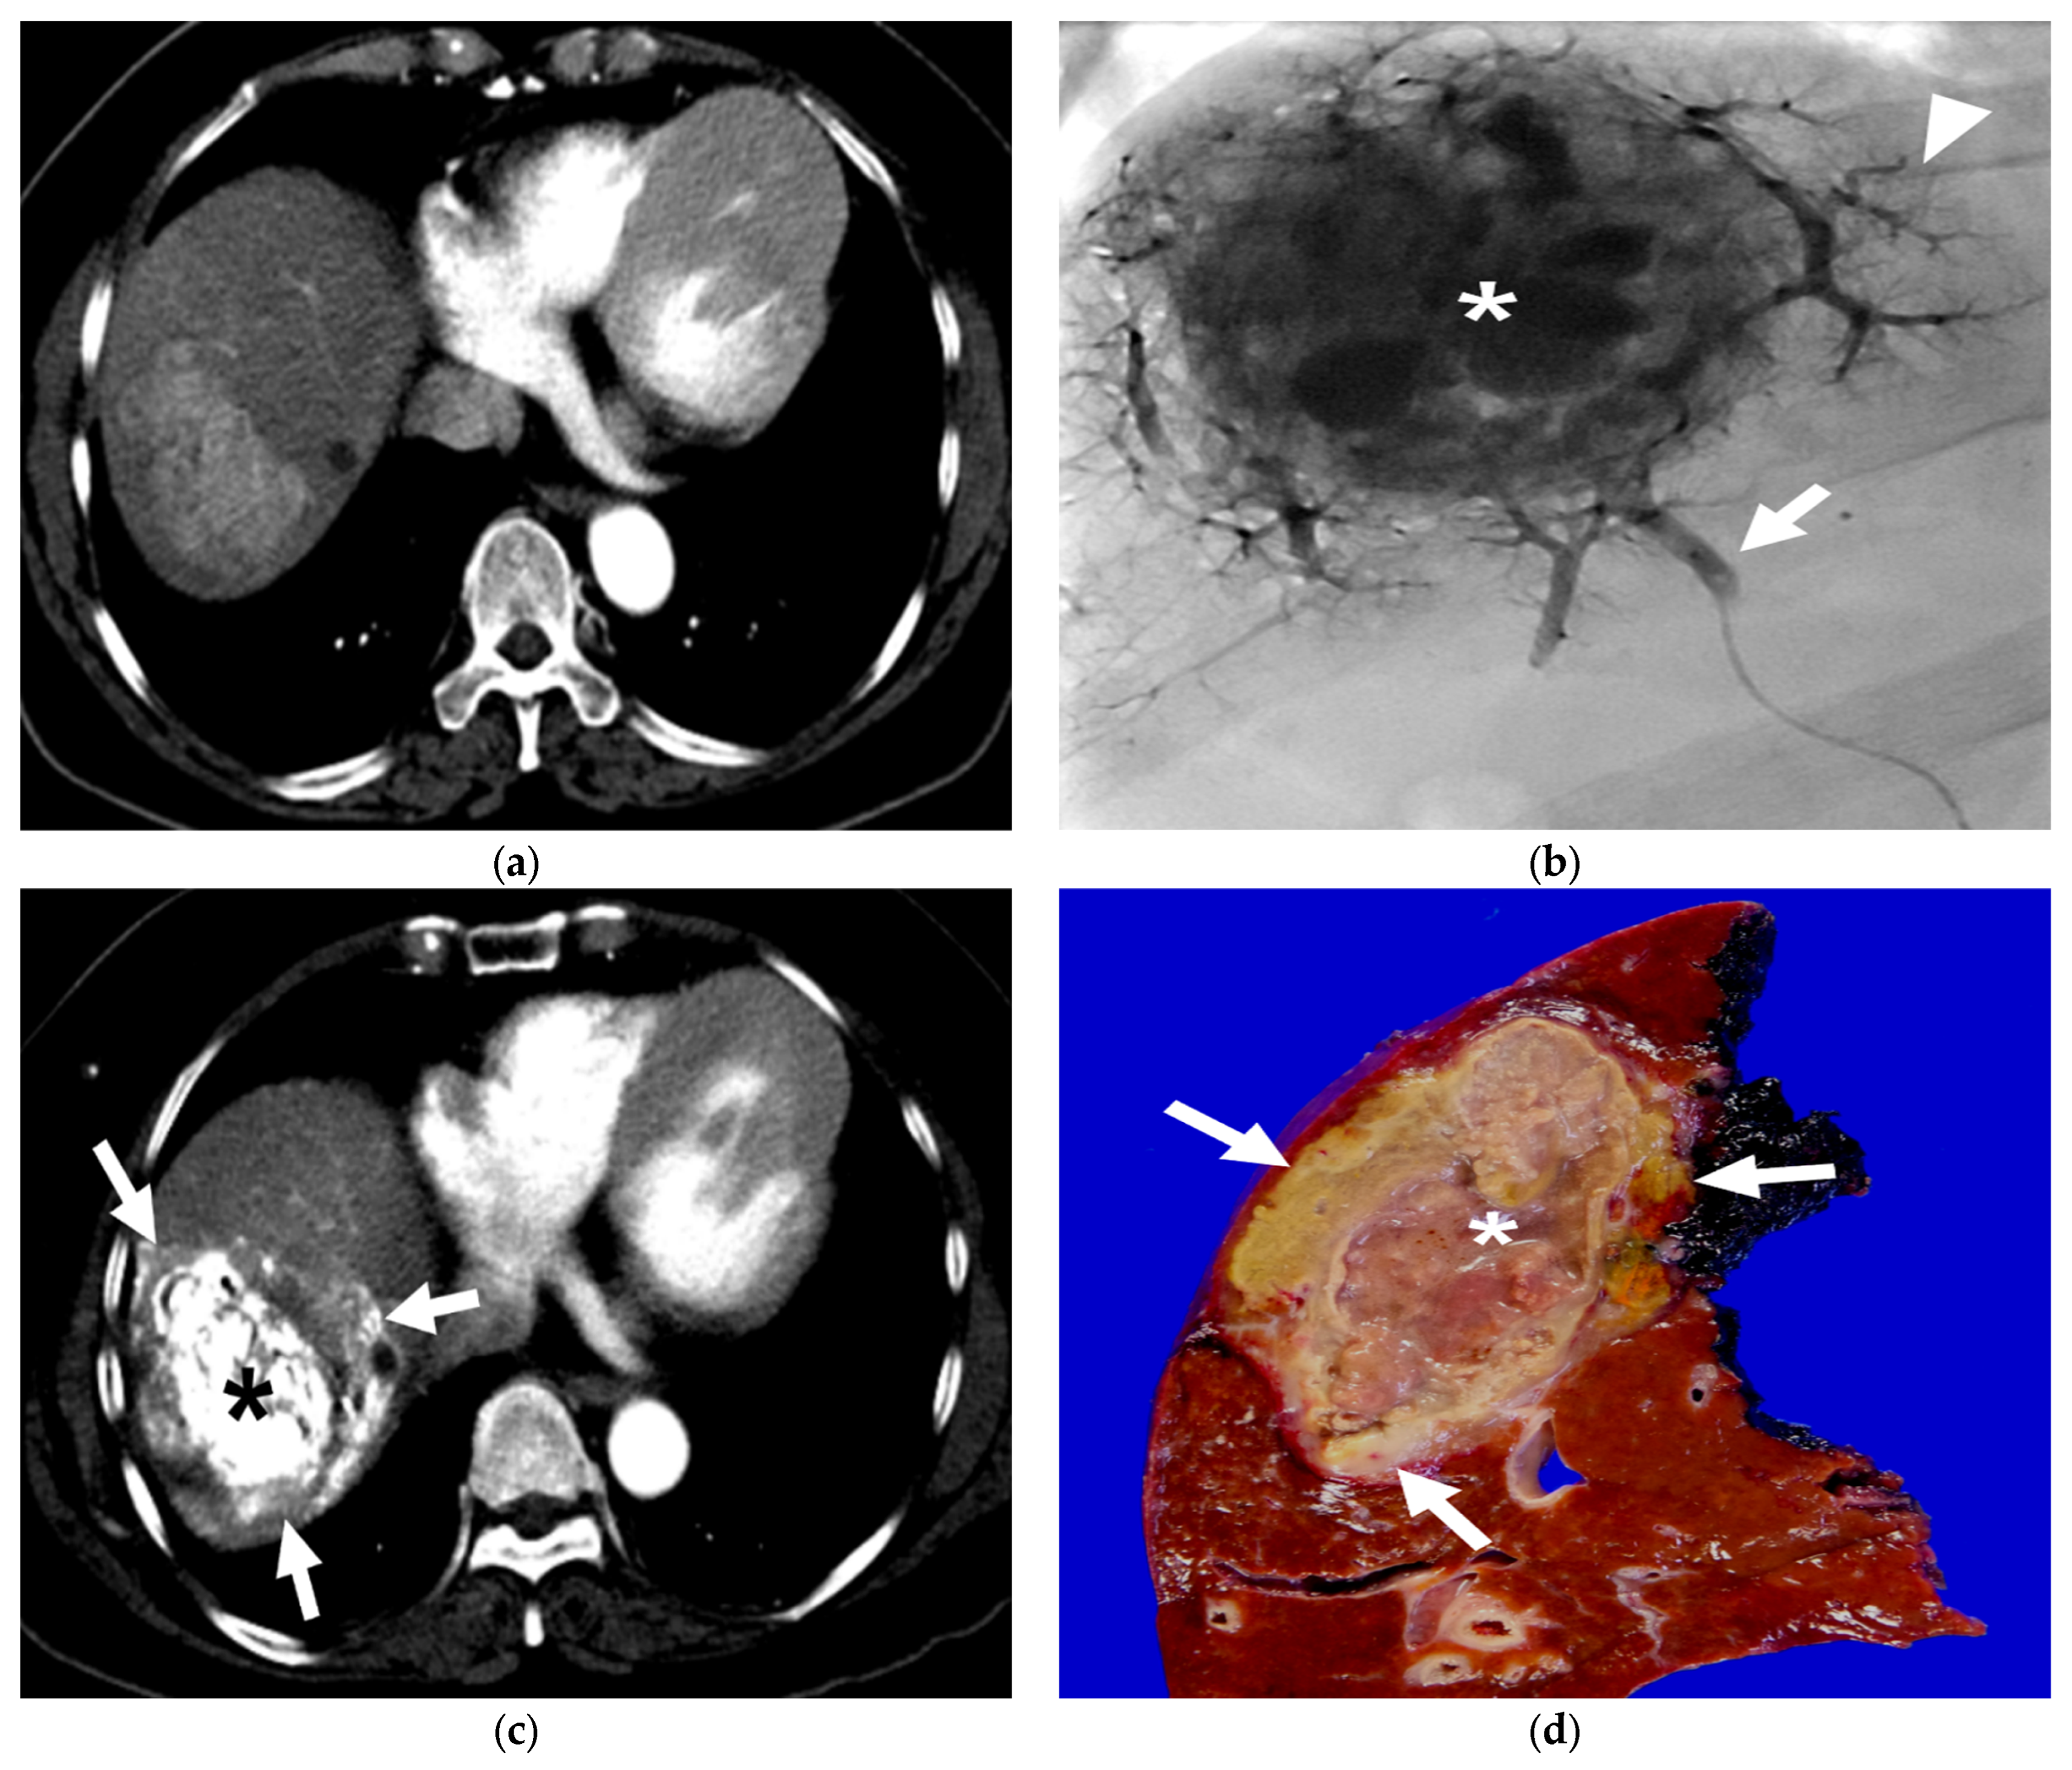

3.1. B-TACE Procedure

3.2. Radiological and Pathological Outcomes